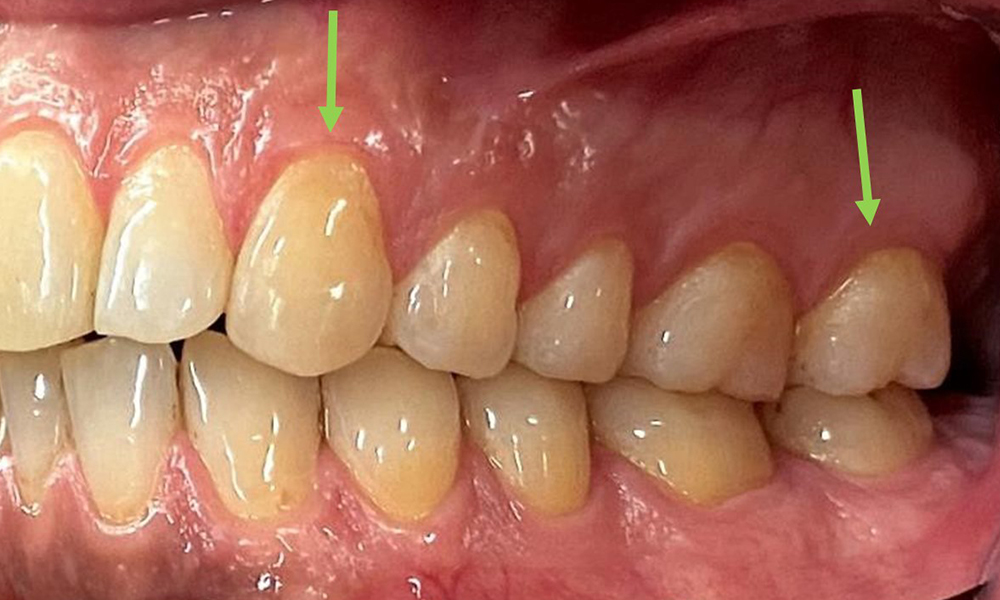

Due to the otherwise favourable general medical condition, the needs determined during the intraoral examination will be decisive for their treatment. It will be essential to periodically determine the probing depths. Gingival bleeding decreases in smokers, which is why the clinical diagnosis of periodontitis can only be made by probing (Fig. 7). Placing exclusive focus on the determination of bleeding indices may obscure existing periodontitis or gingivitis. (5)

Pocket probing (BOP) with depiction of tooth 36 lingual

Fig. 7 Pocket probing (BOP) with depiction of tooth 36 lingual, © Dr R. Krapf